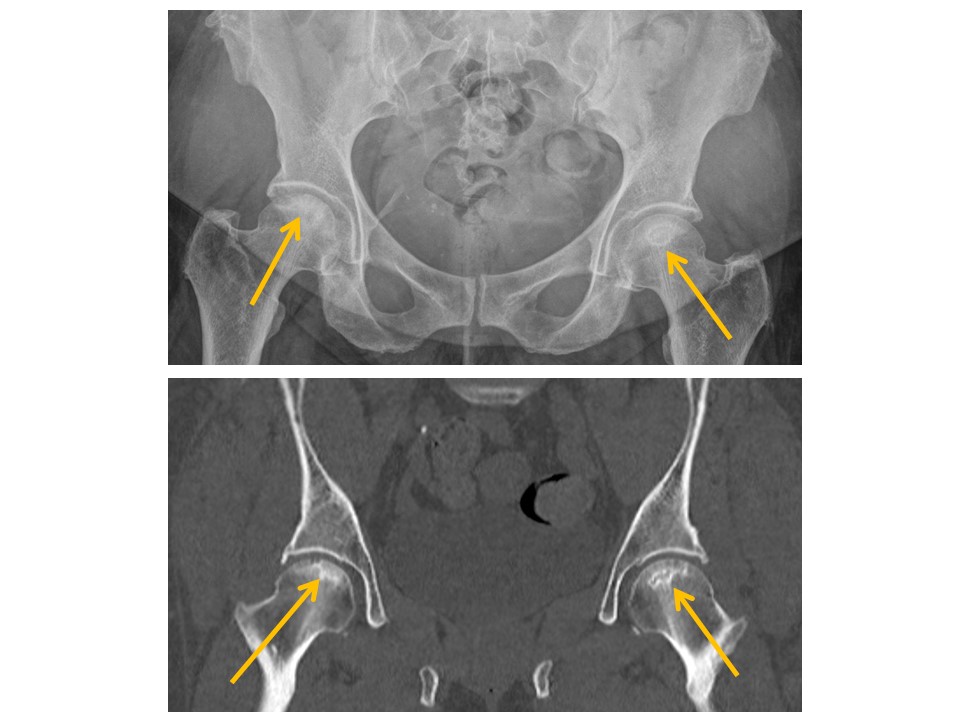

HIPS/PROXIMAL FEMURS

Hip alignment is abnormal. [Yes/No]

There is hip osteoarthritis or inflammation. [Yes/No]

There are hip joint effusions. [Yes/No]

There are intra-articular bodies within the hip joints. [Yes/No]

Femoral head fractures are present. [Yes/No]

Femoral head osteonecrosis is present. [Yes/No]

There are fractures of the femoral neck, intertrochanteric region, or subtrochanteric region. [Yes/No]

There are avulsion fractures of the greater or lesser trochanters. [Yes/No]